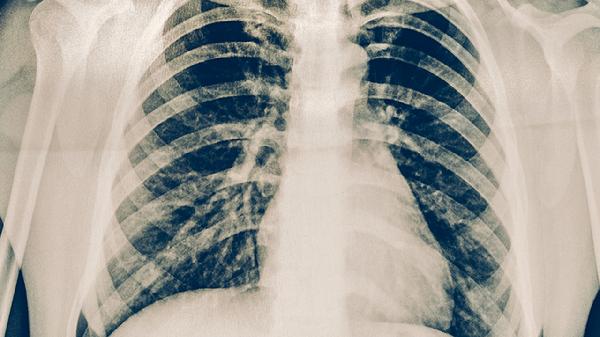

病变范围局限且患者免疫功能正常时,病情通常较轻。这类情况多见于社区获得性肺炎的早期阶段,致病菌常为肺炎链球菌或流感嗜血杆菌等常见病原体。患者可能出现咳嗽、发热、咳痰等典型呼吸道症状,但血氧饱和度维持在正常水平,影像学检查显示肺部浸润影较为局限。治疗以口服抗生素如阿莫西林克拉维酸钾片、左氧氟沙星片为主,配合休息与充足水分摄入,症状多在1至2周内缓解。

若病变范围广泛或合并多重感染,病情可能较重。高龄、存在慢性心肺疾病或免疫功能低下者更易出现这种情况。病原体可能包括耐药菌、病毒或真菌,导致肺部出现大面积实变或胸腔积液。患者常表现为持续高热、呼吸困难、意识模糊等全身中毒症状,甚至引发脓毒症或呼吸衰竭。此类情况需住院接受静脉抗生素如注射用头孢曲松钠联合阿奇霉素治疗,必要时需氧疗或呼吸机支持。

肺炎性病变的诊断需结合胸部影像学与实验室检查,治疗应严格遵循医嘱。日常需注意保暖、避免吸烟、保持室内通风,接种流感疫苗和肺炎疫苗有助于降低感染风险。若出现咳脓痰、胸痛或呼吸急促症状加重,须立即就医。